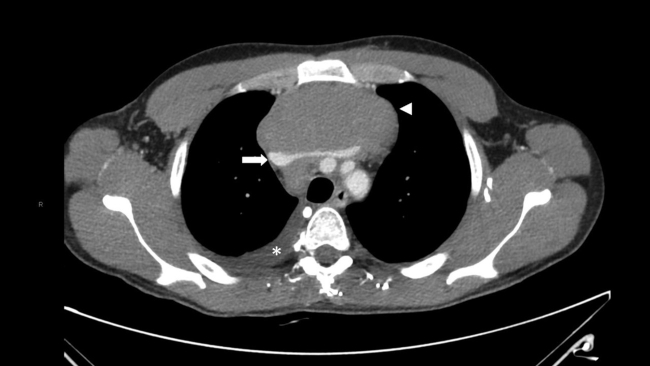

Presentamos el caso de un varón de 30 años que acudió al Servicio de Urgencias de nuestro hospital derivado por su médico de atención primaria, por la presencia de bultomas tumefactos y dolorosos a la palpación, localizados en el cuero cabelludo de un mes de evolución, predominando en zona parietal, temporal y occipital. Asociaba cefalea de características inespecíficas y astenia. Desde hacía dos semanas presentaba nódulos cervicales que impresionaban adenopatías preauriculares, retroauriculares y submandibulares. No presentaba fiebre ni sudoración nocturna. Refería pérdida de 1 a 2 kg en el último mes. Había sido tratado con minociclina 100 mg durante un mes sin mejoría. Durante su estancia, se realizó interconsulta con el Servicio de Dermatología, que completó el estudio con serologías de sífilis, virus de la inmunodeficiencia humana (VIH), hepatitis y citomegalovirus; biopsia de las lesiones de cuero cabelludo, cuyo resultado reveló linfoma / leucemia linfoblástica T; y se practicó punción aspirativa con aguja fina (PAAF) de adenopatía cervical, que confirmó el cuadro linfoide monomorfo. También se solicitó TC toracoabdominopélvica con contraste intravenoso (CIV) que puso de manifiesto: una masa mediastínica anterior que englobaba vasos con leve compresión y desplazamiento sugestiva de conglomerado adenopático y múltiples lesiones focales renales, bilaterales, así como engrosamiento apendicular sugestivos de infiltración linfomatosa (►Figs.1,2a,2b,3a,3b).

Existe una amplia variedad de manifestaciones radiológicas.1,3 La presencia de múltiples lesiones corticales nodulares es la forma más común, como en nuestro caso. Suelen ser bilaterales, de tamaño variable, típicamente de 1 a 4,5 cm de diámetro. Ante dicho hallazgo y los múltiples diagnósticos diferenciales que plantea (metástasis, carcinoma de células renales, pielonefritis, carcinoma de células transicionales, etc.) conviene completar el estudio con biopsia, si es el único hallazgo linfomatoso.2,3 En la TC sin CIV, aparecen como lesiones con una atenuación ligeramente más alta que la del parénquima circundante. La TC con CIV en fase nefrográfica es esencial porque muchas lesiones son pequeñas y afectan a la porción medular de los riñones, con mínima deformidad cortical. Los depósitos linfomatosos realzan menos que el tejido renal normal y aparecen como masas relativamente homogéneas e hipodensas.1,2